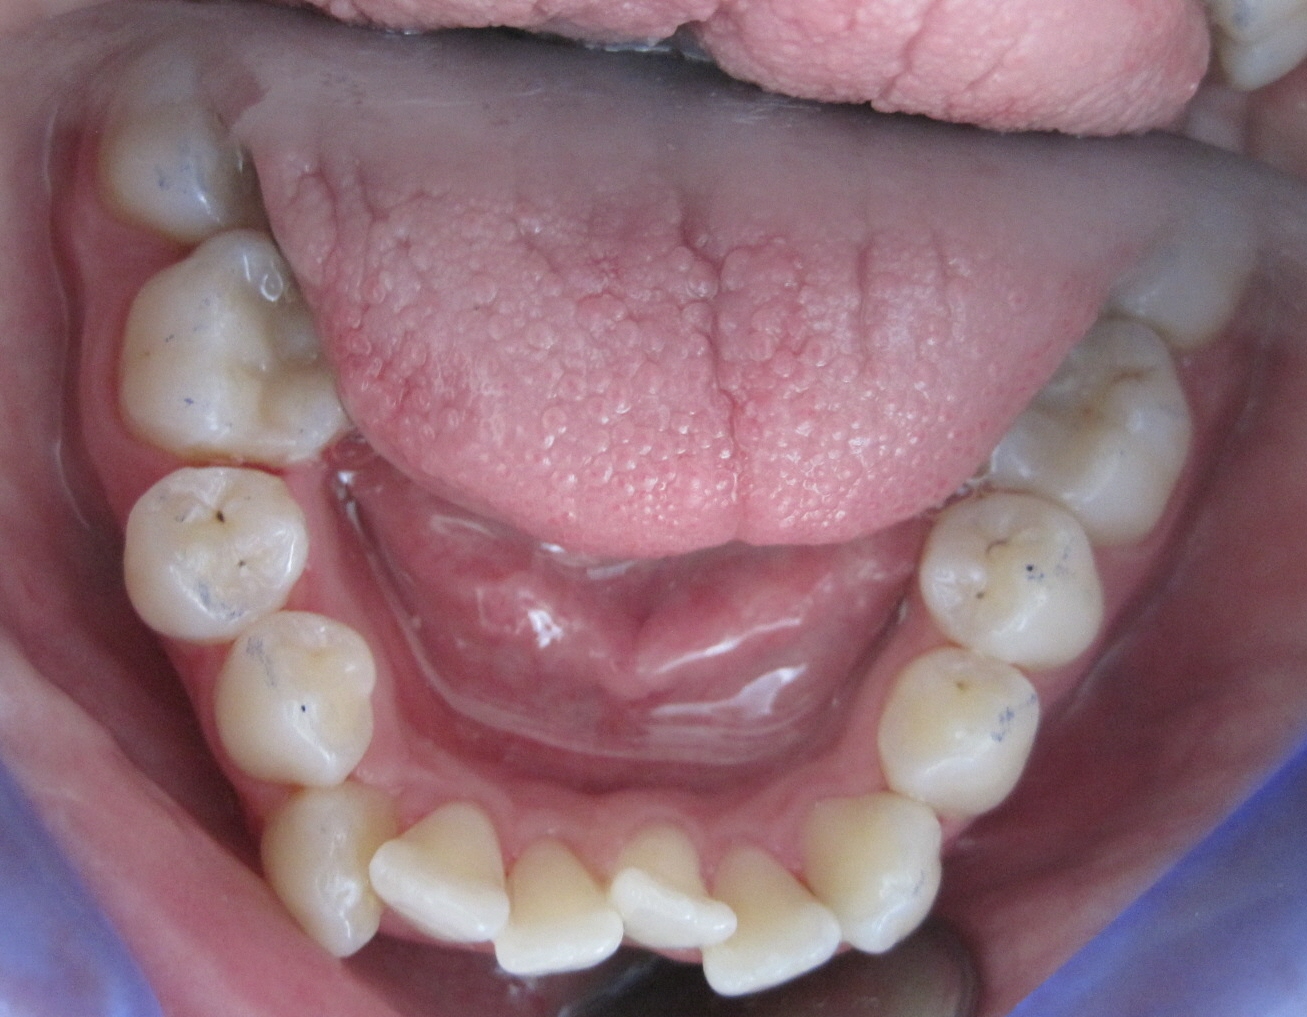

Patient 41 Jahre, massiver Unterkiefer-Frontzahn-Engstand: Alphalignbehandlung mit 15 Alphalignern, d.h. 7,5 Monate Behandlungszeit, jetzt viel bessere Pflege möglich, da akkurater Zahnbogen, dadurch geringeres Risiko von Karies sowie Zahnfleisch- und Zahnbetterkrankungen

vorher